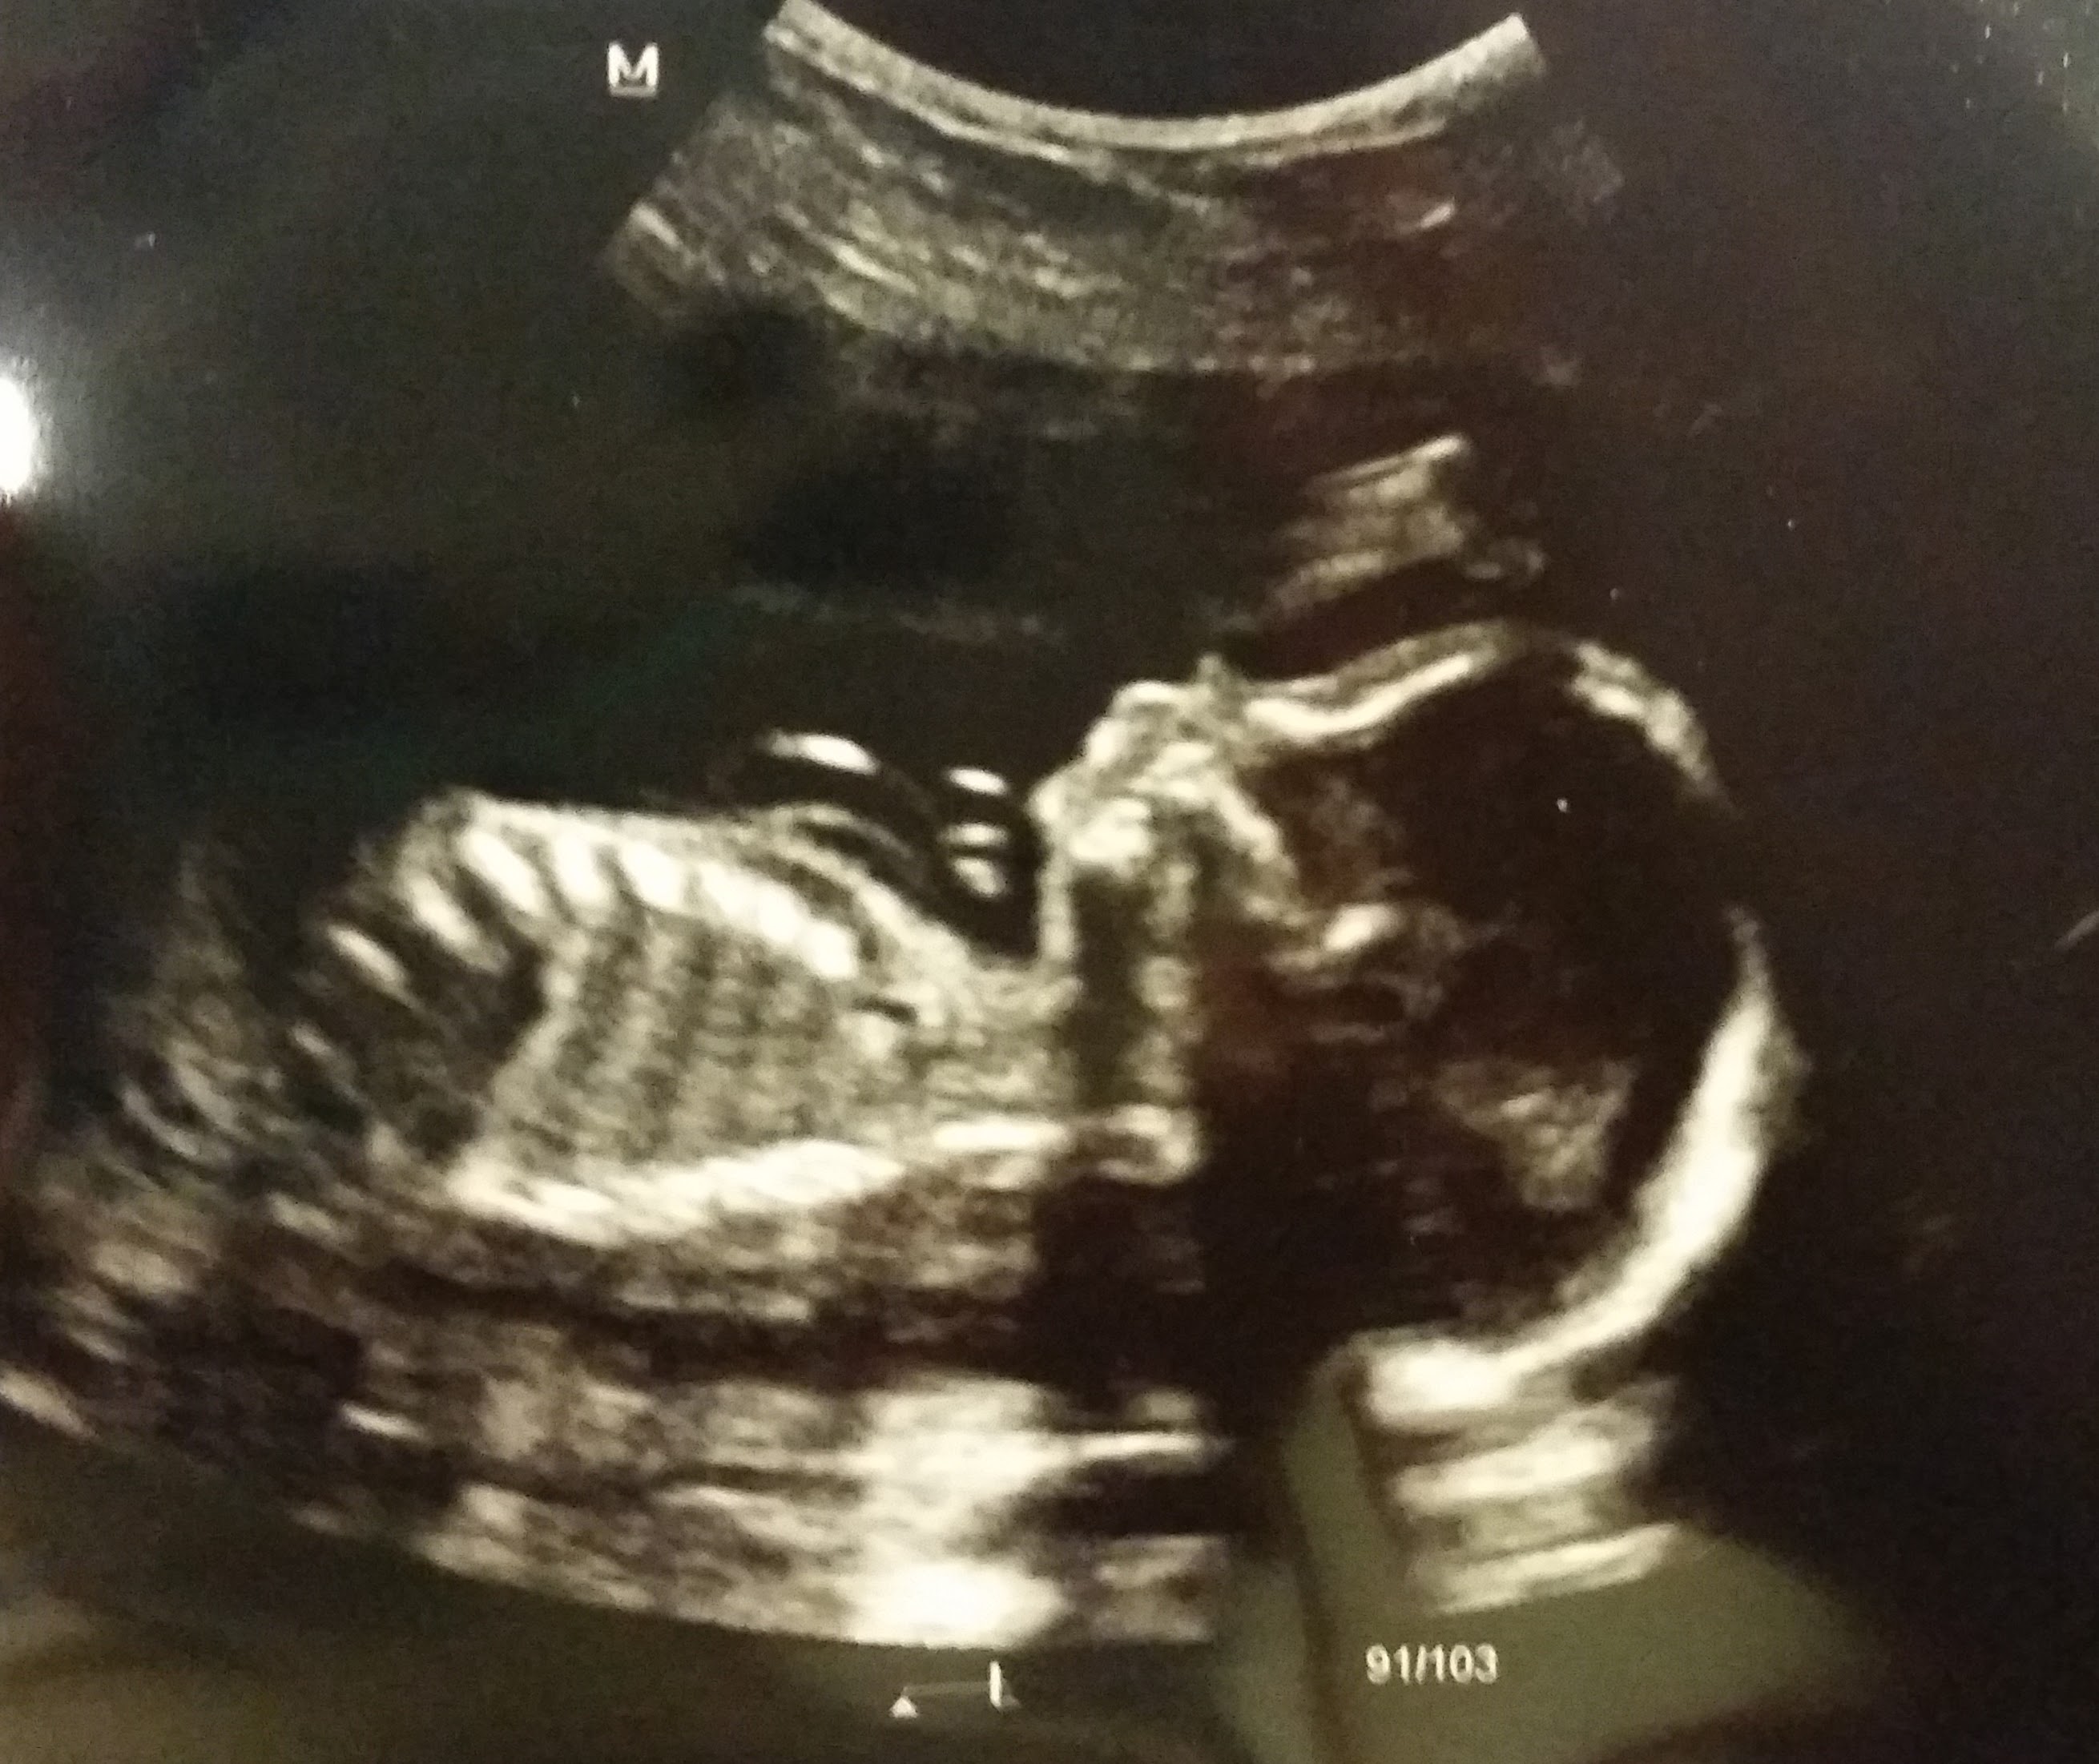

Finalllllly had my anatomy scan. Everything looked good. Tech said he was most definitely a boy, which we already knew. She wasn't able to get a good view of his facial features so we will go back in two weeks to try again. She also saw a subchronic hematoma (sp?). Which I had assumed was from a day of bleeding followed by about 4 days of this nasty dark brown discharge, that we were told was just from a day of hiking while we were on vacation in Vegas. (because it was 100+ degrees) But we have to go see someone else about that.

• Had my scan and my baby boy was very uncooperative with his positioning. All he did was flash us his boy bits (we already knew it was a boy) and then turned away. I'll have to return for part 2 next week to finish checking 2 more organs.

• Doc said the baby looked great. Very active with a good heart rate. He was transverse so we got a good look at his manly bits. Doc said they were pretty sizable.

• I had a gender scan at 16 weeks (it's a boy!) but just had my 20 week anatomy scan and he's looking perfect and healthy too! And stubborn lol he kept pushing against the ultrasound tech when she pushed down lol.